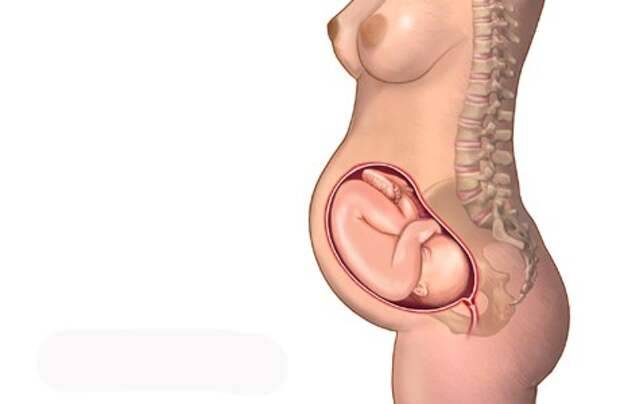

Удивительные моменты девятого месяца беременности на фотографиях

Раздел: Снимки-откровения